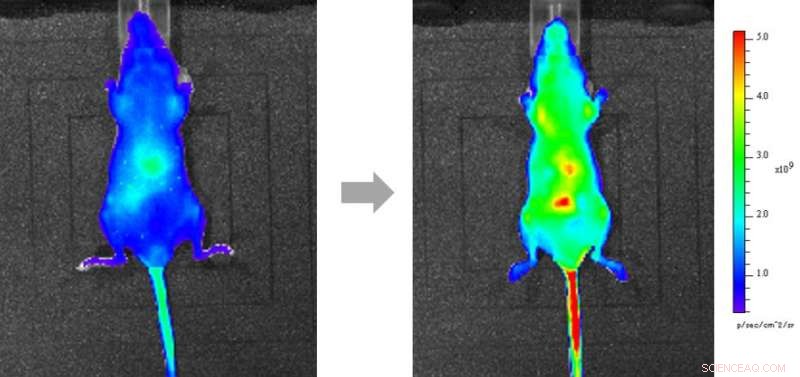

The mice were injected with a dose of extra Vitamin C, raising the concentration above normal. The probe signal spread throughout the body over one hour, becoming particularly intense in vital organs. This is the first time that researchers have directly imaged Vitamin C administered to a mouse. Credit: 2017 Kazuyuki Ishii, Institute Of Industrial Science, The University Of Tokyo

Next, the mice were injected with a dose of extra ascorbic acid, raising the concentration above normal. Within 10 minutes, the fluorescence signal flared up in the abdomen - showing that this was the first destination of the ascorbic acid dose flowing from the tail. Like before, the probe signal then spread throughout the body over the next hour, becoming particularly intense in vital organs. This is the first time that researchers have directly imaged ascorbic acid administered to a mouse.